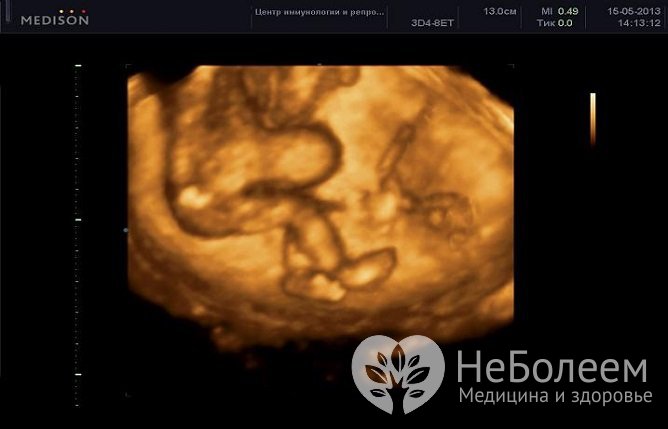

Омфалоцеле диагностируется на этапе внутриутробного развития плодаЭмбриональные пупочные грыжи в большинстве случаев диагностируются на этапе внутриутробного развития ребенка при проведении планового ультразвукового исследования.